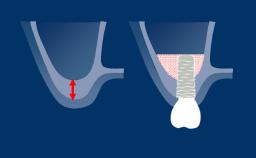

成功的种植治疗需要以修复为导向制定种植计划,以确定理想的种植体位置。种植体的位置应方便戴入理想的最终修复体,而理想的修复体应能满足功能性和美观性需求并模拟天然牙列。

通过辅助诊断检查,可确定和评估位点特定的外科和修复要求。这有助于尽量减少种植治疗后的并发症和失败风险。